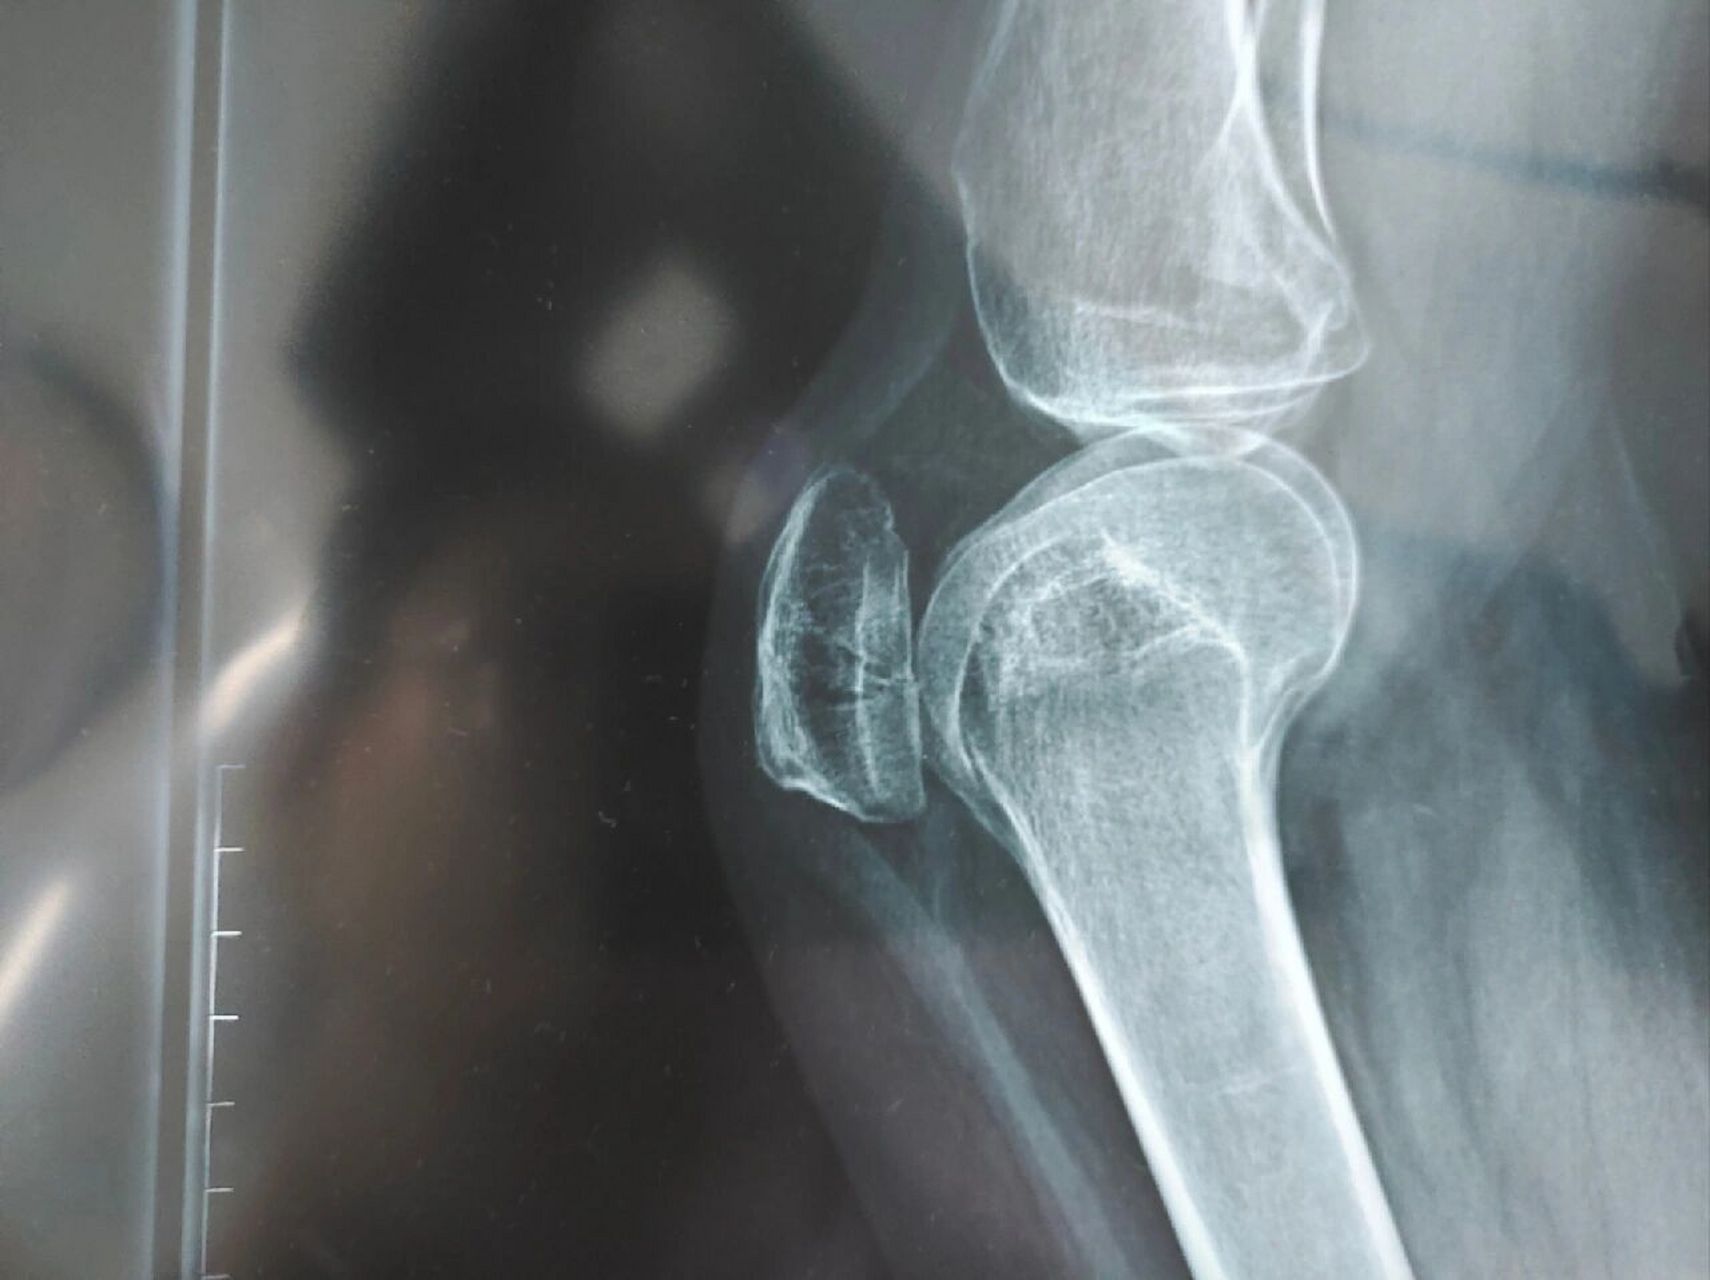

髌骨纵行骨折,侧位不能显示

图片尺寸1600x1200